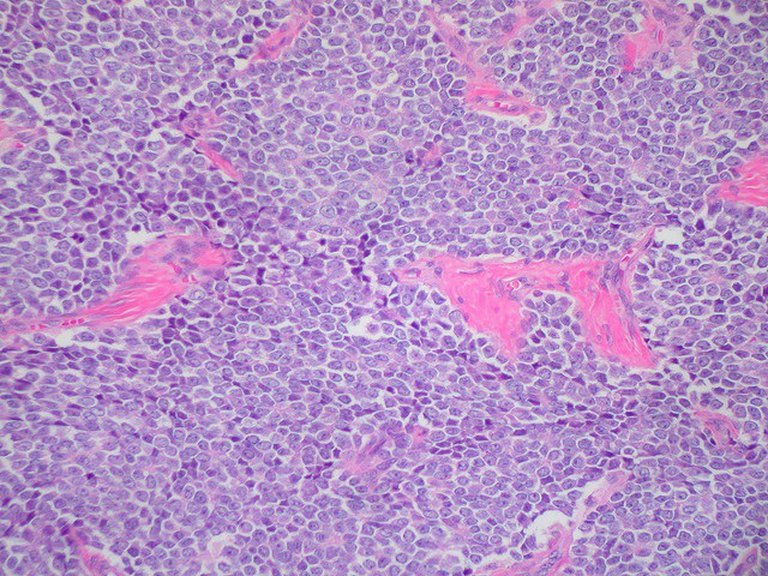

Cada 13 de julio se conmemora el Día Internacional del Sarcoma, una afección con baja incidencia y tratamiento multidisciplinario. Se trata de un tipo de tumor poco frecuente, que padecen alrededor de cinco personas cada 100 mil al año. Hay más de 150 tipos y se desarrolla tanto en huesos como en tejidos blandos del organismo

Los sarcomas son un grupo heterogéneo de tumores que pueden aparecer a partir de distintos tejidos y en diversas partes del cuerpo, aunque aproximadamente el 60% de ellos se presenta en brazos o piernas, el 30% en tronco o abdomen y el 10% en cabeza o cuello.

A grandes rasgos, existen dos grupos:

1. Sarcomas de partes blandas (SPB). Son los que se desarrollan en los tejidos blandos del organismo como los músculos, tendones o grasa. Son tumores poco frecuentes. Constituyen aproximadamente un 1% del total de tumores malignos, y son responsables del 2% de la mortalidad debida a cáncer.

2. Sarcomas óseos. Son tumores muy infrecuentes y afectan sobre todo a niños y adolescentes, con una incidencia que se estima en un paciente nuevo por año por cada 100 mil habitantes. A pesar de su rareza, constituyen la quinta causa de cáncer en adolescentes y jóvenes entre 15 a 19 años.:quality(85)/cloudfront-us-east-1.images.arcpublishing.com/infobae/ONSYANHPFRALJH65FKLSTVHD7I.jpg%20420w) Existen dos grupos de sarcoma (Foto: Getty Images)